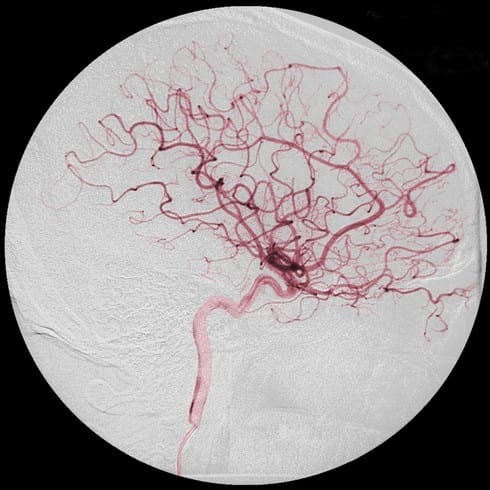

Тонкая и чувствительная кожа часто страдает от воздействия внешних факторов и реагирует на их проявления покраснением и воспалением. В дальнейшем развивается купероз – сосудистое заболевание, являющееся следствием нарушений в эпидермисе кровообращения, из-за чего развивается застой в капиллярах крови.

Сам по себе купероз не представляет опасности для здоровья человека, но внешние его проявления выглядят весьма не эстетично и часто становятся причиной развития комплексов и различных психологических проблем. Избавиться от купероза возможно, если установить точную причину появления патологии и своевременно начать лечение.

При куперозе происходит ослабление капиллярных стенок, из-за чего мышечные волокна парализуются.

Сосуды, близкие к эпидермису, наполняются кровью и остаются без движения, поэтому на лице становится видная сосудистая сеточка, заметны покраснения, особенно в области щек и носа.

Приток крови, давление, оказываемое на стенки капилляров, еще больше растягивают их. В результате под тонкой кожей четко видны признаки купероза – красноватые прожилки, переплетающиеся между собой, образующие узелки и «звездочки».

Если говорить о лице, то чаще всего появляется купероз на носу и щеках. Кожа в этих местах сухая, подверженная раздражению, появляется зуд и жжение, ощущение дискомфорта.